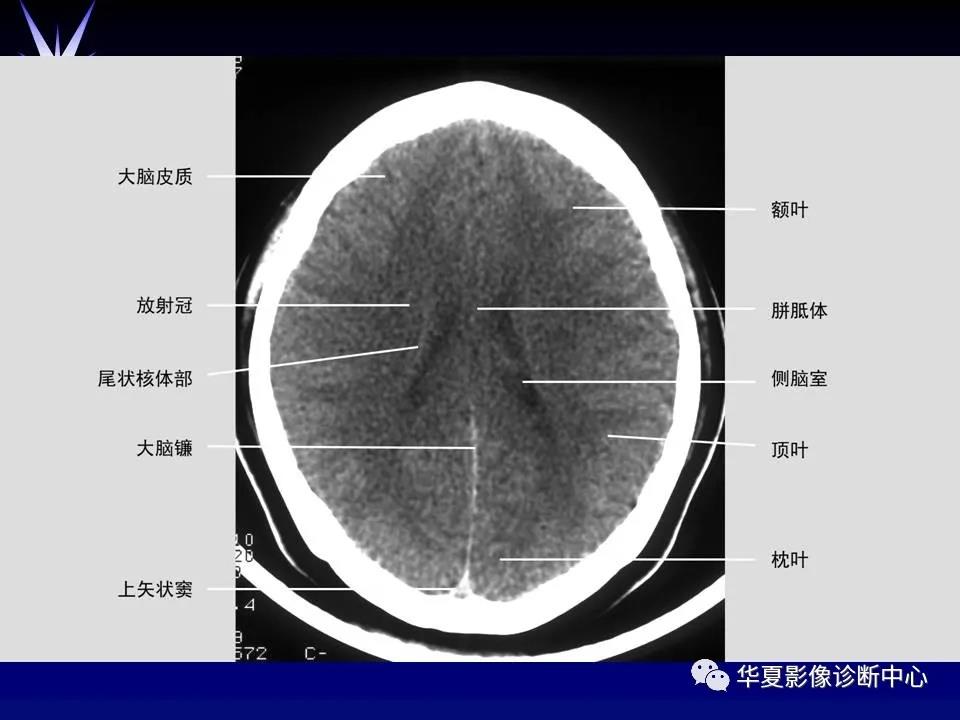

来源:华夏影像诊断中心